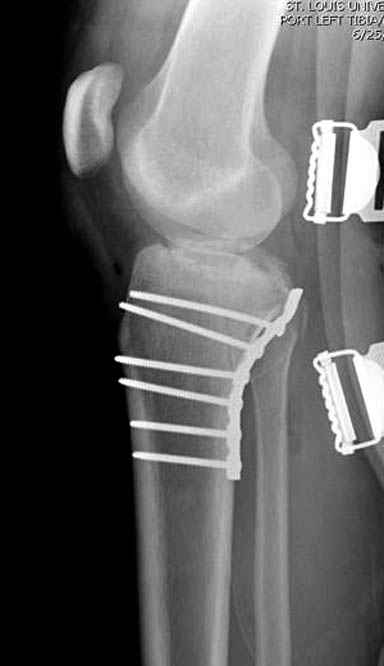

Уважаемые коллеги! В прошлую пятницу больной прооперирован - как и планировалось мыщелковая LCP от ChM. Малоинвазивно не получилось - один большой доступ :(. (но с минимальным скелетированием б/б кости). Наружный мыщелок собрали, но по контролю видно, что задне-медиальный отдел метаэпифиза смещен. Фиксировать не стали (?). 4-е сутки после операции - по м/тканям без проблем. Дополнительная иммобилизация синтетическим тутором.

P. S. перелом диафиза на контроле не совсем захвачен, но проблем там нет. Приношу извинения за низкое качество Р-грамм - выполнены на сканере (фотоаппарат не работает :)) .

Трудно поверить, что разрекламированная Ортопедическая школа Восточной Украины позволяет такие странные снимки? На прямом снимке сохранен общий контур плато, но не известна судьба импрессии суставной поверхности. На полубоковой?, оставлен без репозиции задне-медиальный отдел, и навряд ли после такой фиксации можно удовлетвориться результатом.

Такая ситуация характерна для многих, когда принимается ошибочное решение, т.е пытаются фиксировать одним имплантом переломы двух мыщелков. Латеральная пластина приемлема только для тех случаев, когда сохраняется интактным медиальный диафизарный кортекс и отсутствует фрагментация на верхушке медиального перелома.